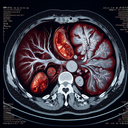

МРТ печінки

Магнітно-резонансна томографія (МРТ) печінки – це неінвазивне діагностичне обстеження, яке використовує магнітні поля та радіохвилі для створення детальних зображень печінки. Це дослідження допомагає лікарям оцінити стан органу та виявити різні патології. Ось основні випадки, коли проводиться МРТ печінки: 1...